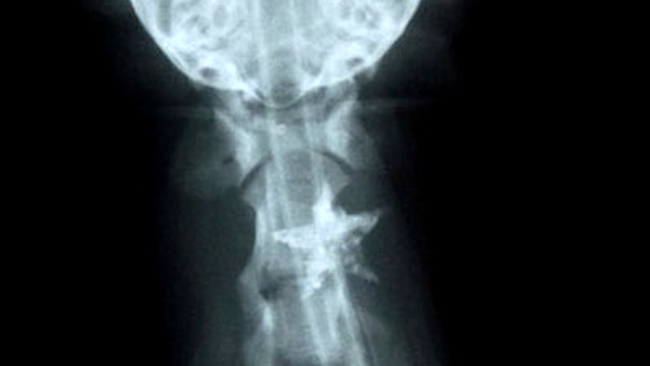

Cele mai ciudate obiecte descoperite la radiografii (Poze)

Radiologii raman uimiti cand vad in radiografia unui pacient obiecte care in mod obisnuit nu ar trebui sa se afle acolo.

Cazurile in care o persoana si-a batut un cui in cap sau in ochi, si-a introdus o sticla in anus sau a inghitit chei sunt uimitoare chiar si pentru doctori.

Medicii radiologi raman muti de uimire cand vad in radiografia unui pacient obiecte care in mod obisnuit nu ar trebui sa se afle acolo.

Cunoastem ca toti copii au o placere deosebita in a inghiti tot felul de obiecte, insa ei sunt absolviti de vina. Cum categorisim adultii care, din diferite motive, ajung in asemenea ipostaze?